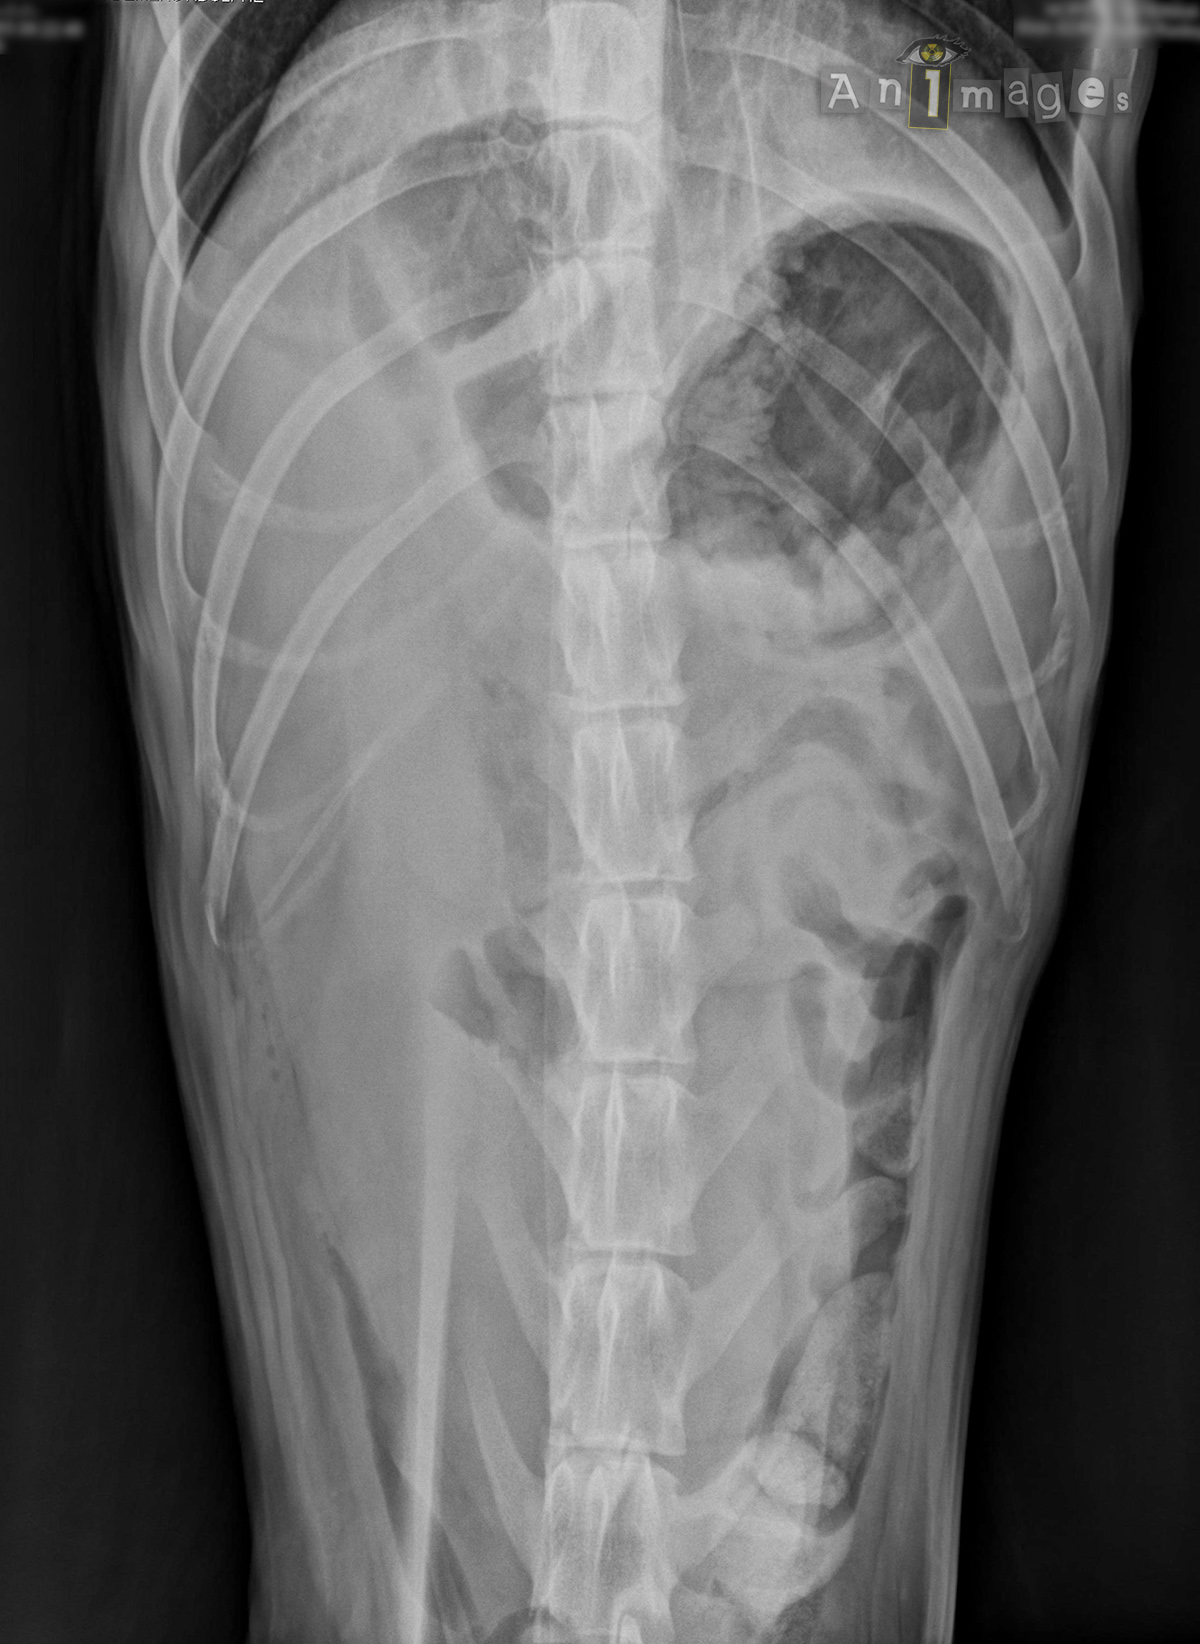

Ventrodorsale